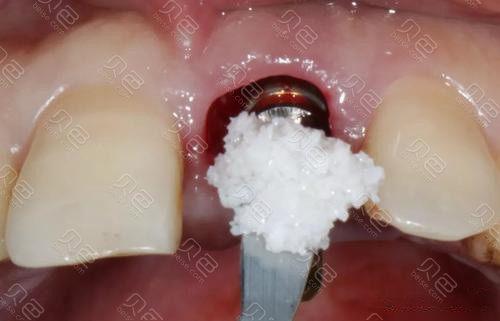

- 植入骨粉:将处理好的骨颗粒填入缺损处,避免过度挤压,确保材料均匀分布。

- 覆盖屏障膜:部分情况下需覆盖可吸收胶原膜,防止软组织长入骨区,为骨细胞再生提供空间。